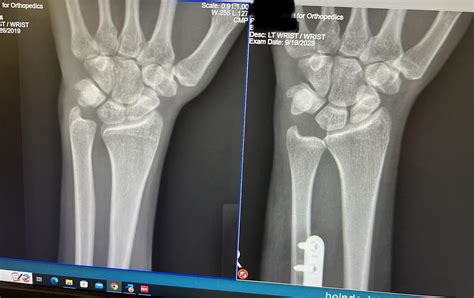

If conservative efforts fail to provide relief after several months, or if significant structural damage is identified, surgery may be necessary. The goal of surgery is to decompress the ulnar side of the wrist by correcting the length discrepancy.

• Ulnar Shortening Osteotomy: This is the most common surgical procedure for Positive Ulnar Variance. A small portion of the ulna bone is removed to shorten it, and the bone is then secured with a plate and screws. This effectively brings the ulna back to a neutral or slightly negative position, offloading the joint.

Regardless of whether you choose conservative treatment or surgery, consistency is key. Following your healthcare provider's guidelines is paramount for a successful outcome. If surgery is performed, adhering strictly to post-operative rehabilitation protocols will ensure proper bone healing and functional restoration of the wrist.